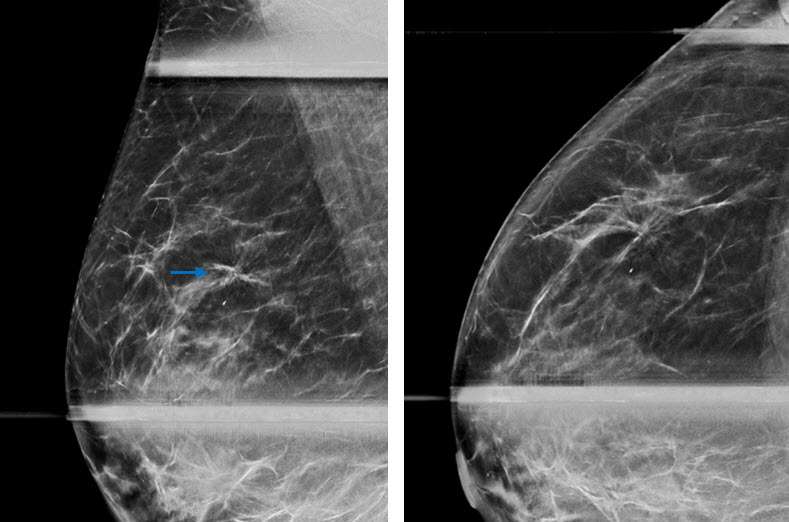

Mammography:

Radial sclerosing lesions are often identified incidentally on screening mammograms. There is robust evidence that digital breast tomosynthesis improves the detection and characterization of RSLs compared to digital mammography (4). The radiographic appearance of RSLs may be indistinguishable from that of invasive carcinoma, thus needle biopsy is essential in excluding malignancy.

Radial sclerosing lesions may be multiple and/or bilateral. The most typical appearance is an architectural distortion or the “black star” configuration, which is defined as spiculations radiating from a central point without a central mass (Fig 1a). However, the presence of a radiolucent center is not reliable in differentiating a RSL from malignancy (1). Less frequently, RSLs may appear as a stellate opacity or the “white star,” which is described as a mass with spiked linear extensions (3).